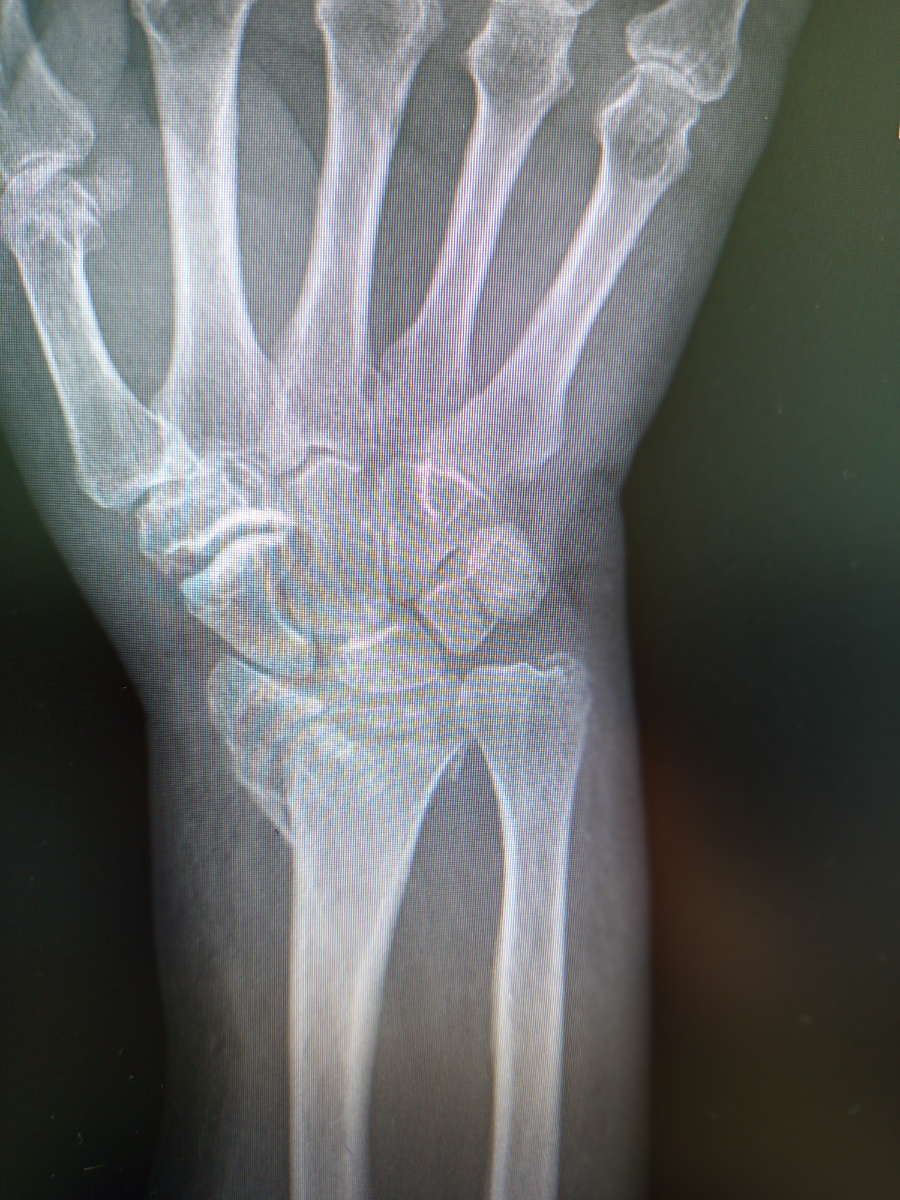

Бабуля зашла, луч сломала.

Парень, 22 года, в прошлом году катался на лыжах, споткнувшись, получил перелом обеих берцовок.

Поставили ему интрамедуллярный стержень.

После нескольких контролей по истечении года ,стержень наконец-то уберут. Только лег на стол, как спрашивает:

–А можно посмотреть снимок?

–Да погоди ты! Я еще сама их не видела и не делала!

–А как сделаете , покажете?

–Да , покажу покажу, лежи уже спокойно.

Сделала , как обещала, веду показать снимок.

–Это срослась уже?

–Срослась , не видишь что ли?

–А маленькая что так криво срослась?

–Так , все вопросы к врачу!Со спортом , надеюсь , завяжешь?

–Вот еще! Я и в этом году уже катался!

Ну , да , костей же много, не на одну травму хватит.